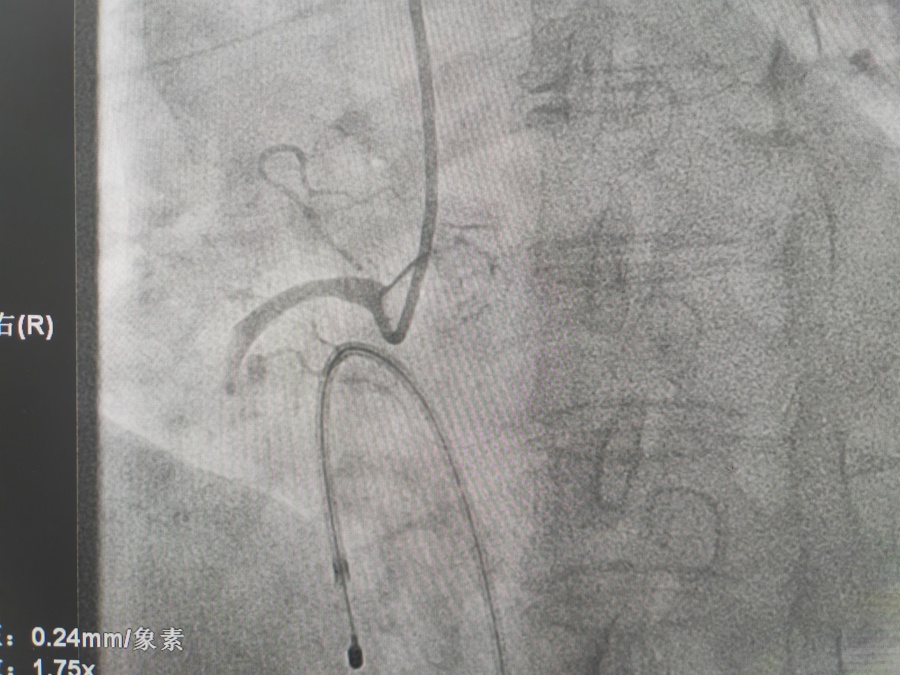

冠心病的治疗

冠脉支架置入术是将以不锈钢或合金材料刻制或绕制成管状而其管壁星网状带有间隙的支架(药物支架),置入冠状动脉内已经或未经PTCA扩张的狭容节段支撑血管壁,维持血流畅通。因球囊扩张后,约20-40%的病变会发生再狭窄,有些会发生急性冠脉闭塞而导致急性心肌梗死或死亡,所以在扩张后,多致需要再用冠脉内支架将病变处永久性撑开,即支架置入。置入支架是为了减少斑块撕袭后塌陷,急性塞,增加手术安全性,减少再狭窄。目前PTCA加上支架置入术已成为治疗冠心病的重要手段。